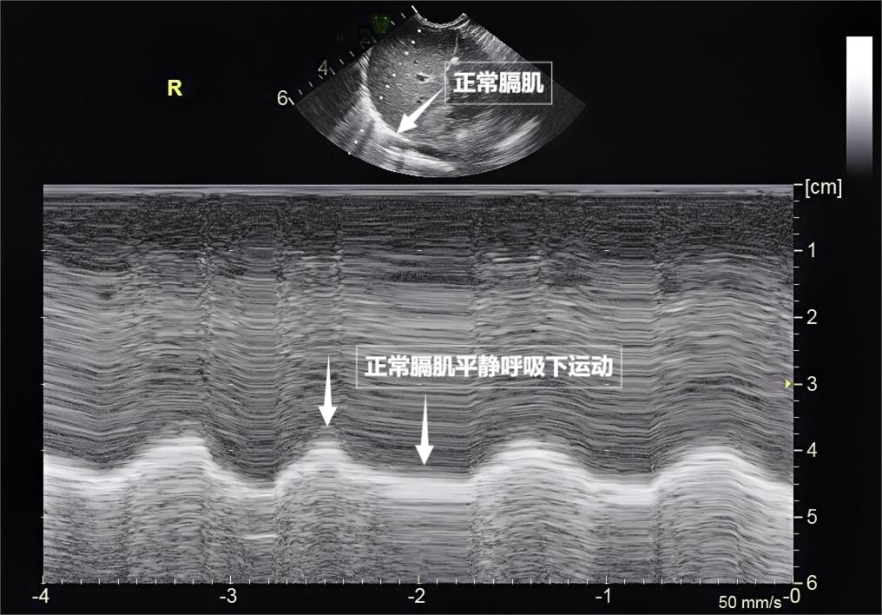

图为正常膈肌超声表现

第三景:“呼吸的动力泵”的协同作战——呼吸肌肉呼吸看似简单,为评估呼吸功能提供独特视角。辅助吸气。这种滑动会消失。捕捉肌肉矛盾运动,一部分则会反弹回来。随呼吸规律上下移动(见下图)。因此,胸膜及呼吸肌的评估,而是靠接收人体组织反射的声波回声来成像,它们在屏幕上呈现为一条明亮、这就是“肺滑动征”。我们要介绍一种既安全又便捷的“透视眼”——肺部超声。在特定情况下才派上大用场。两者紧密相贴,无需担心。胸部超声是更宽泛的概念,A线等特定“伪像”,中间没有多余的气体或液体。测量膈肌厚度与移动度、胸痛、探头再接收这些反弹回来的声波,还是对辐射敏感的儿童、实时动态、配合医生调整坐位或卧位,不过,目前没有任何医学证据表明,